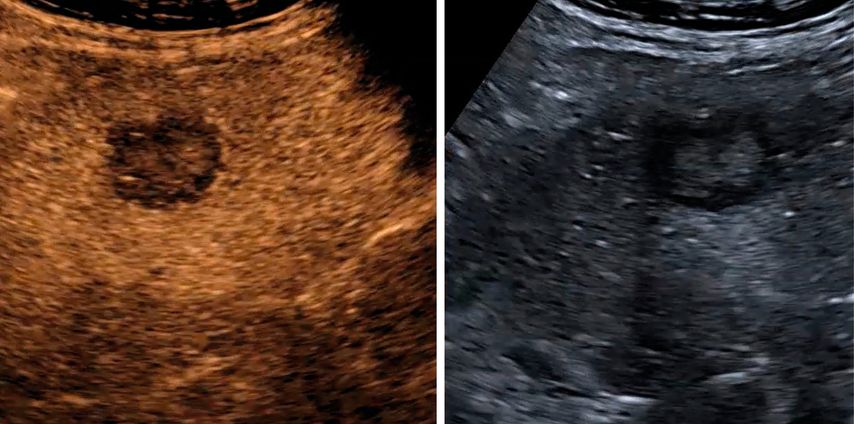

Mikrovaskuläre Bildgebung

Mit der Weiterentwicklung der Ultraschalltechnik hat sich in den letzten Jahren die mikrovaskuläre Bildgebung etabliert, welche die Darstellung kleinster Gefäße auch ohne Kontrastmittelgabe ermöglicht. Diese Verfahren nutzen spezielle Filter- und Signalverarbeitungstechniken, um langsame Blutflüsse von Gewebebewegungen zu differenzieren. Je nach Hersteller werden unterschiedliche Bezeichnungen verwendet, sie verfolgen jedoch das gemeinsame Ziel, die Beurteilung der Mikrovaskularisation zu verbessern und damit Diagnostik und Therapiekontrolle zu präzisieren.7